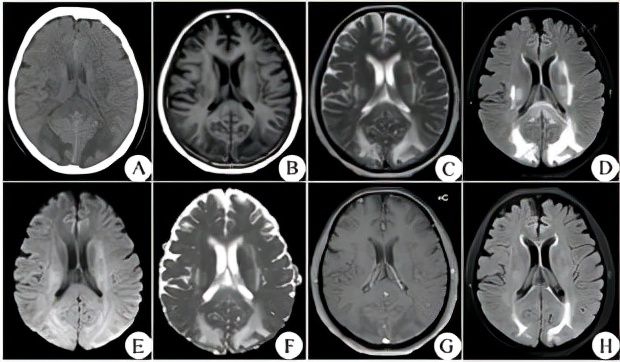

患者否认高血压病史,遂请神经内科及眼科医师会诊。查阅护理记录发现,患者近1周内血压在参考范围内且较平稳(图1)。查体:生命体征平稳,精神反应较差,意识清楚,能简单作答,查体合作;右眼视力:眼前指数;左眼视力:眼前指数;视野检查不配合;眼压:指测正常;双眼前节及眼底未见明显异常;双侧瞳孔等大同圆,直径约为3.0 mm,直接及间接对光反射灵敏;双眼球各向运动正常,未见眼震;双侧额纹、鼻唇沟对称,伸舌居中;脑膜刺激征(-);四肢肌张力、肌力正常;四肢腱反射对称、正常;双侧病理征未引出。患者于2018-06-21 17:00行生化检查,结果示血钾为3.7 mmol/L,血钠为129 mmol/L,血氯为97 mmol/L,血钙为1.96 mmol/L,渗透压为278 MoSM/L,白蛋白为29.8 g/L,尿素氮为0.92 mmol/L,肌酐为27 μmol/L;急行颅脑CT检查提示:(1)左侧大脑半球脑肿胀,少量蛛网膜下腔出血;(2)双侧顶枕叶皮质下、放射冠及基底核区异常密度影(图2)。综合查体、生化检查及颅脑CT检查结果,考虑患者双眼视物模糊伴头痛为低钠血症所致RPLS可能性大,遂予以脱水、营养神经、维持水电解质平衡及一般对症支持处理。患者于2018-06-23复查血钠、渗透压均恢复正常(表1),2018-06-25行颅脑MRI检查提示:(1)胼胝体压部、双侧内囊后肢、外囊、基底核区、双侧额顶枕叶脑白质变性,脑血管增强成像未见明显异常。经治疗后患者视物模糊、头痛等症状逐渐好转,2018-06-30视力恢复正常且无视物模糊、头痛等症状;2018-07-09复查颅脑MRI示双侧侧脑室后角旁白质、顶枕叶异常信号,双侧枕叶皮质下及基底核区白质病变范围较前缩小,符合RPLS影像学变化规律(图2)。

图2

患者颅脑CT及MRI检查结果

Figure 2

Craniocerebral CT and MRI imaging findings of the patient

除了病因学方面的鉴别诊断外,RPLS的典型影像学表现——可逆的对称性大脑后部白质病变还需与中枢神经系统脱髓鞘疾病、急性脑梗死(如基底动脉尖综合征)、其他代谢性脑病、急性播散性脑脊髓炎、颅内静脉窦血栓形成等脑白质病变相鉴别,并需结合患者病史、临床表现、影像学表现及病情演变规律等进行综合判断。在临床上,RPLS最容易与急性脑梗死相混淆,颅脑MRI弥散加权成像(DWI)、表观弥散系数(ADC)序列有助于二者的鉴别诊断:急性脑梗死患者为细胞毒性水肿,MRI表现为DWI高信号、ADC低信号,而RPLS患者为血管源性水肿,MRI多表现为DWI等信号或低信号、ADC高信号。本例患者颅脑MRI表现及演变提示双侧枕叶皮质下及基底核区白质病变呈可逆性的血管源性水肿表现,符合RPLS影像学表现及变化规律。